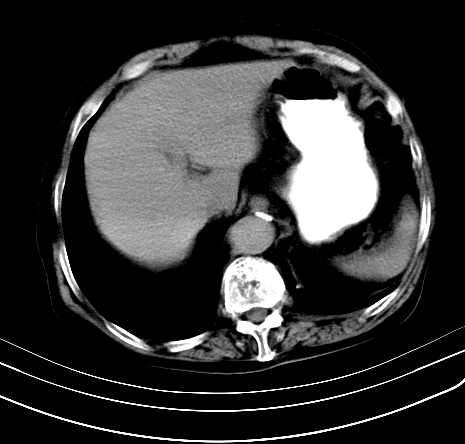

上腹部疼痛不适,行ct检查

慢性胰腺炎,假囊肿形成,脂肪肝。

考虑慢性胰腺炎假性囊肿形成,不除外胰腺癌粘液状乳头状瘤可能。建议增强必要时ercp检查。